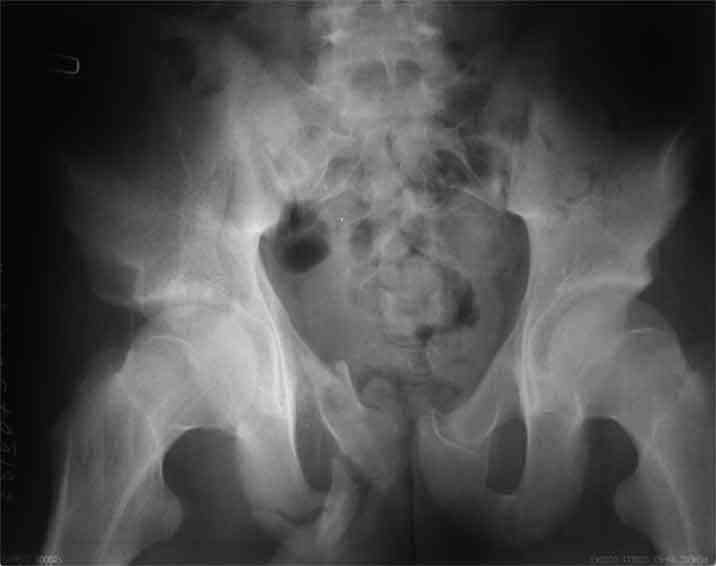

А чего там собственно таинственного? Билатеральное ротационно-нестабильное повреждение таза, перелом крестца в I зоне (по Denis)справа,частичное повреждение левого КПС, оскольчатые переломы лонной, седалищной костей справа (В3.2). Повреждение достаточно стабильное + молодой возраст+ сроки - оперативного лечения не требует.

Не смог разглядеть на представленных картинках частичное повреждение левого КП, повреждение Денис1-2 справа? 3Д реконструкции в инлет и боковой проекциях убедительно не демонстрируют типа повреждения задних отделов тазового кольца(справа боковая масса скомпремирована), Наверное, у тебя есть возможность оценить тип перелома крестца по прямой проекции 3Д.

по Pennal et al.- латеральное компрессионное повреждение тип В(ротационно-нестабильное (внутренняя ротация), вертикально стабильное)

по Tile classif. тип В2-1 - частично стабильное повреждение с неполным разрывом задней дуги.

По вертлуге- смог разглядеть только изолированный перелом передней колонны.

Насколько я понял из твоего письма, обращенного к анонимному vit, ты не видишь показаний к реконструкции перелома. Я бы взялся за реконструкцию(илео-ингвинальный доступ), хоть прошел и месяц после травмы: боковая 3Д показывает смещение нагрузочной зоны впадины, что однозначно будет способствовать разрушению хряща головки и впадины( особенно у 16 летнего пациента с ожидаемым высоким уровнем активности) + изменение геометрии впадины за счет неустраненного смещения фрагментов колонны (КТ, 3Д данные).

Недавно наблюдал этого пациента - жалоб на тазобедренный сустав вообще никаких, ходит без хромоты, рентгенологических признаков быстрого развития остеоартроза нет, хотя, конечно, срок наблюдения маловат (месяца 4).

По представленным материалам, мне кажется, перелом был передней колонны ацетабулум с минимальным вовлечением нагрузочной поверхности сустава, левосторенний повреждение КПС и лонных костей.